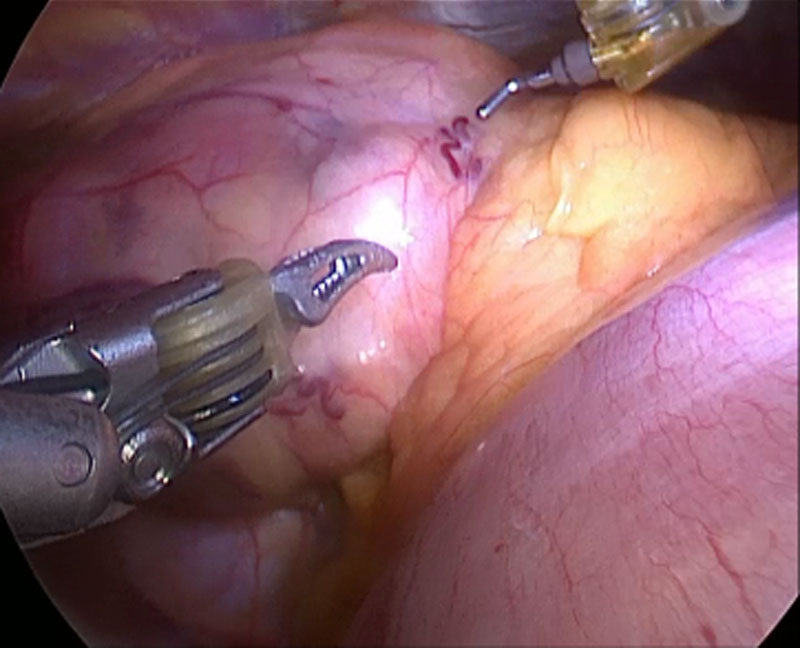

В Пироговском Центре комплексной бригадой эндокринных и торакальных хирургов проведена очередная эксклюзивная операция по удалению внутригрудного зоба больших размеров с интраоперационным нейромониторингом.

В Пироговском Центре начали проводить трансоральные эндовидеоскопические операции на щитовидной железе.

Проведены операции с применением роботизированного хирургического комплекса «Da Vinci» при опухолях средостения — вилочковой железы

Первая робот-ассистированная тиреоидэктомия аксиллярным доступом на хирургическом комплексе Da Vinci